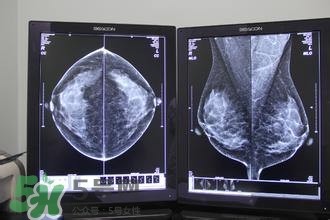

最準(zhǔn)的方式,去醫(yī)院照彩超,乳腺層和脂肪層一目了然。乳腺層的厚度會隨著月經(jīng)周期有微小的變化。

怎么減肥胸部不會變?。繙p肥不減胸的最好辦法